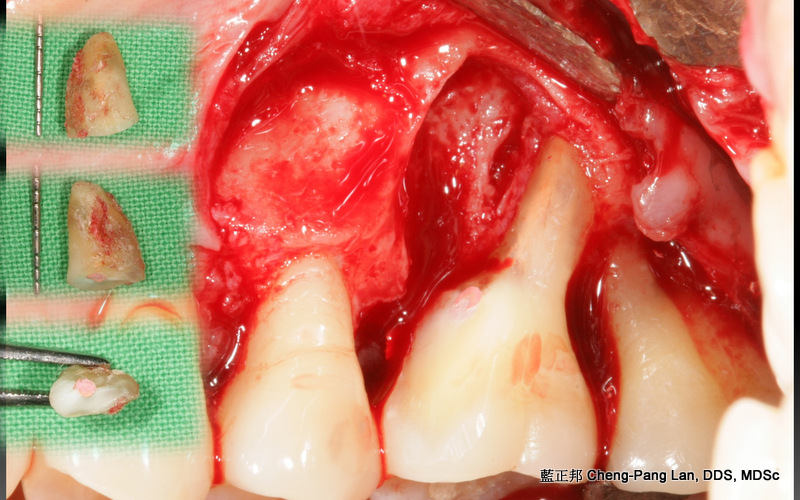

拔牙或植牙?

老師常常暗示著大家,implant與natural teeth之間,留下natural teeth比較好。這個我真的相信,在牙周病科的每一位學弟妹也都相信,甚至我相信週六在場的牙周病醫師都認同,但是大家有沒有想過,每隔週三一起開會的Prosthodontist、 Orthodontist都相信嗎?甚至,從實習醫師畢業就進入職場服務病人的學弟妹們,都相信嗎?